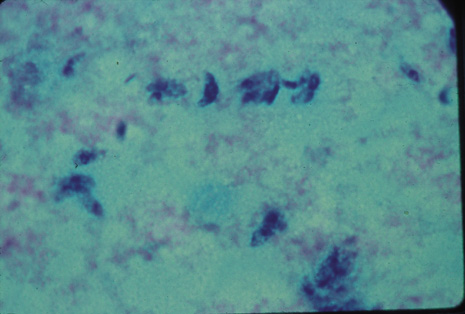

Although keratocentesis had been advocated historically as a treatment for active uveitis, it lost the attention of ophthalmologists until 1919, when Bruckner3 first examined the aqueous humor for diagnostic purposes. Laboratory techniques were revolutionized in the 20th century in areas such as: (a) evaluating very small aliquots of fluid (0.2 to 0.3 mL of aqueous or vitreous), and (b) identifying specific microbial organisms and the predominance of other cell types, antibodies, and proteins in these fluids (Figs. 1, 2, 3, 4, 5, and 6). These advancements have led to the development of diagnostic paracentesis for sight-threatening ocular inflammations that are difficult to diagnose. Witmer4 and O'Connor5 have provided strong evidence that samples of the aqueous humor reflect the antibody-producing capabilities of the iris and ciliary body, particularly when more specific antibody per unit of gamma globulin can be found on the aqueous humor than in the blood of the same patient.6–8 These determinations may be highly significant when one considers the fact that diseased tissue is being bathed in an antibody-containing fluid that is elaborated locally. For instance, in the case shown in Figure 1, the immunofluorescent antibody titer to toxoplasmosis is four times greater in the vitreous aspirate at the time of vitrectomy for repair of retinal detachment than in the plasma. These same considerations have long been recognized in syphilis of the central nervous system, wherein specific antibodies may be present in the cerebrospinal fluid but not in the blood. This is also the case with an unusual presentation of ocular coccidioidomycosis9 or toxocariasis.